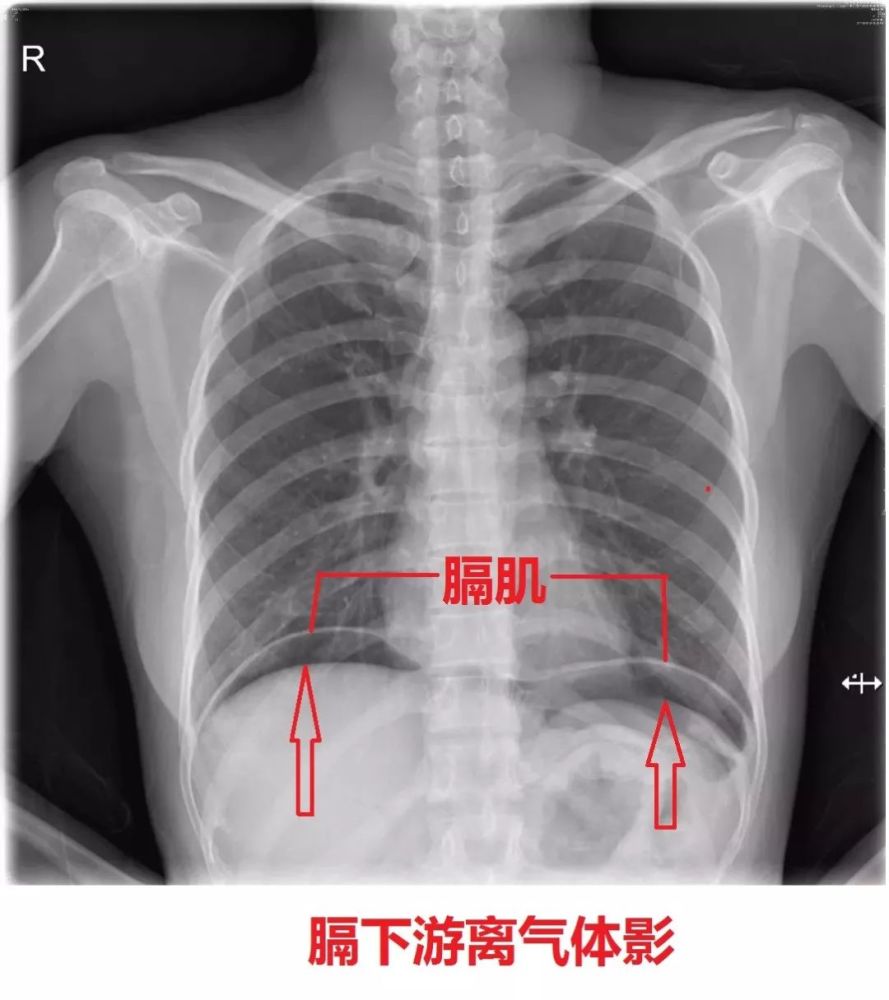

膈下游离气体!

膈肌